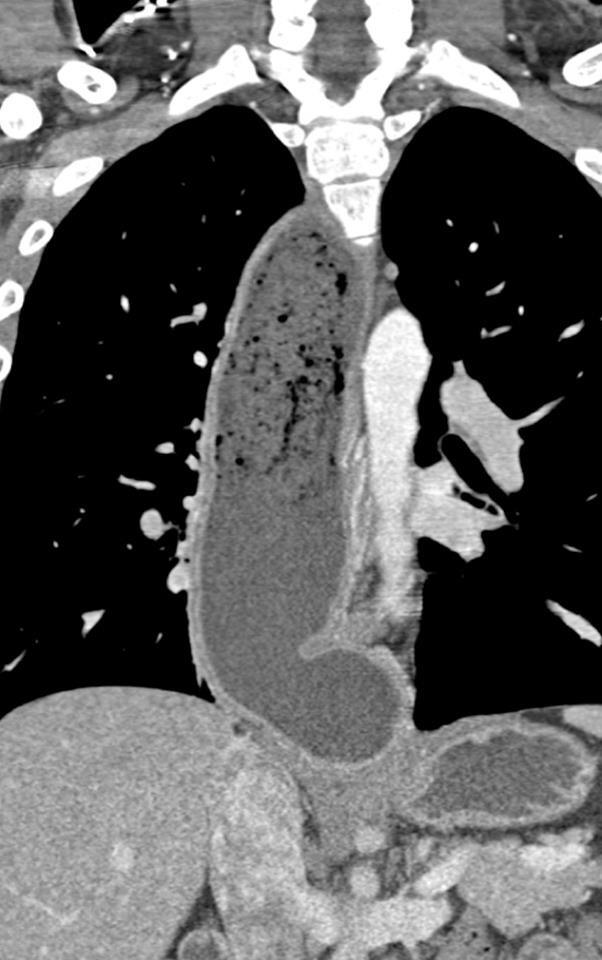

TC DE TORAX .

La Acalasia es un trastorno poco frecuente, que dificulta el paso de alimentos y líquidos hacia el estómago. La acalasia se presenta cuando se dañan los nervios del esófago. En consecuencia, el esófago pierde la capacidad de empujar el alimento hacia abajo, y la válvula muscular que se encuentra entre el esófago y el estómago( esfínter esofágico inferior) no se relaja por completo, lo que dificulta que el alimento llegue al estómago.